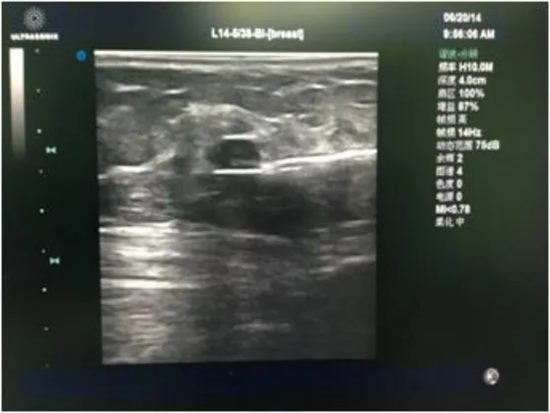

2.超声引导下的“精准狙击”

手术全程在实时超声的可视化引导下进行。

不仅能精确定位结节位置、大小,更能靶向切除病变组织,尽可能避免“误伤”正常乳腺组织。